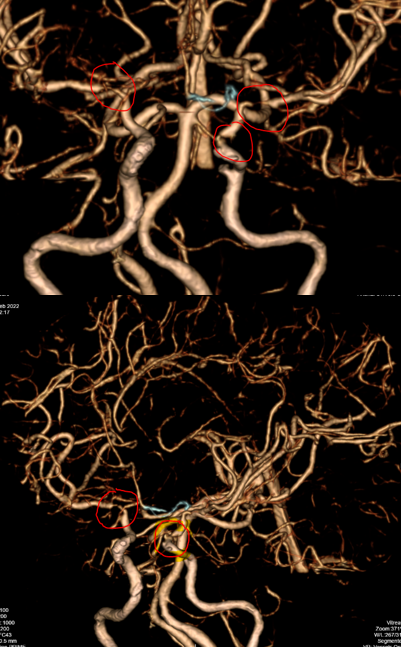

Bệnh nhân tiếp tục được được chụp CLVT mạch máu não: Phát hiện hẹp khít động mạch cảnh trong trái đoạn mấu giường và động mạch não giữa đoạn M1 hai bên.

Một bệnh nhân trẻ tuổi, CLVT mạch máu não nghĩ nhiều đến hình ảnh của bệnh Moya Moya, vì vậy bệnh nhân được chỉ định chụp DSA mạch não để khẳng định chẩn đoán đồng thời tiên lượng khả năng điều trị bệnh.

Hình chụp DSA động mạch cảnh trong phải và trái: hẹp khít động mạch não giữa hai bên đoạn M1.

Hình chụp DSA động mạch cảnh trong trái: hẹp khít động mạch cảnh trong trái đoạn mấu giường.

Hình chụp DSA động mạch đốt sống: bàng hệ cho hệ tuần hoàn trước từ hệ thống tuần hoàn sau

2. CHẨN ĐOÁN: hình ảnh điển hình của bệnh Moya Moya